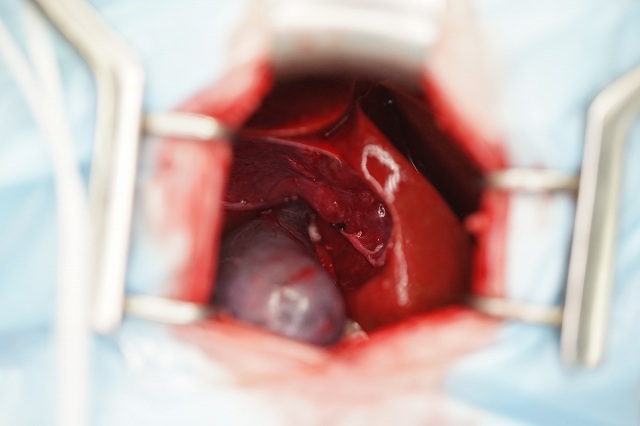

胆嚢摘出術(開腹)

慢性炎症により肝臓への癒着が強い場合、胆嚢破裂を伴ったり、総胆管閉塞が強い場合は、開腹手術が適応になります。